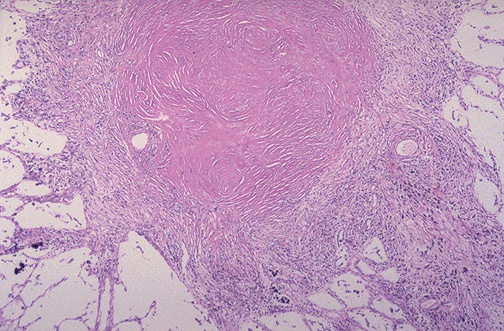

A silicotic nodule in lung is seen here. It is composed mainly of bundles of interlacing pink collagen. There is a minimal inflammatory reaction. The greater the degree of exposure to silica and increasing length of exposure determine the amount of silicotic nodule formation and the degree of restrictive lung disease. Silicosis increases the risk for lung carcinoma only about 2-fold. |